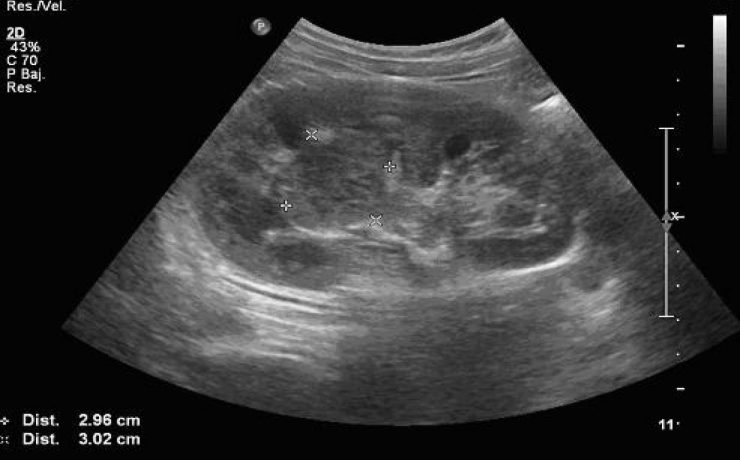

La incidencia de coledocolitiasis después de la intervención quirúrgica tiene una incidencia del 10 porciento, Los cálculos pueden permanecer por años dentro de la vía extra hepática y no manifestar síntomas. Los cálculos pequeños pueden pasar por el colédoco y el duodeno sin producir síntomas (menores 3mm), solo que se